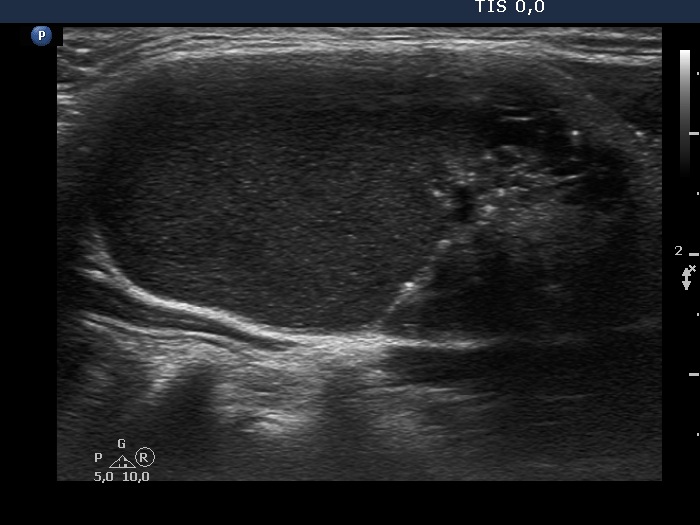

The composition of the nodule - case 126 (ultrasonographic picture 5)

Left lobe, another longitudinal scan.